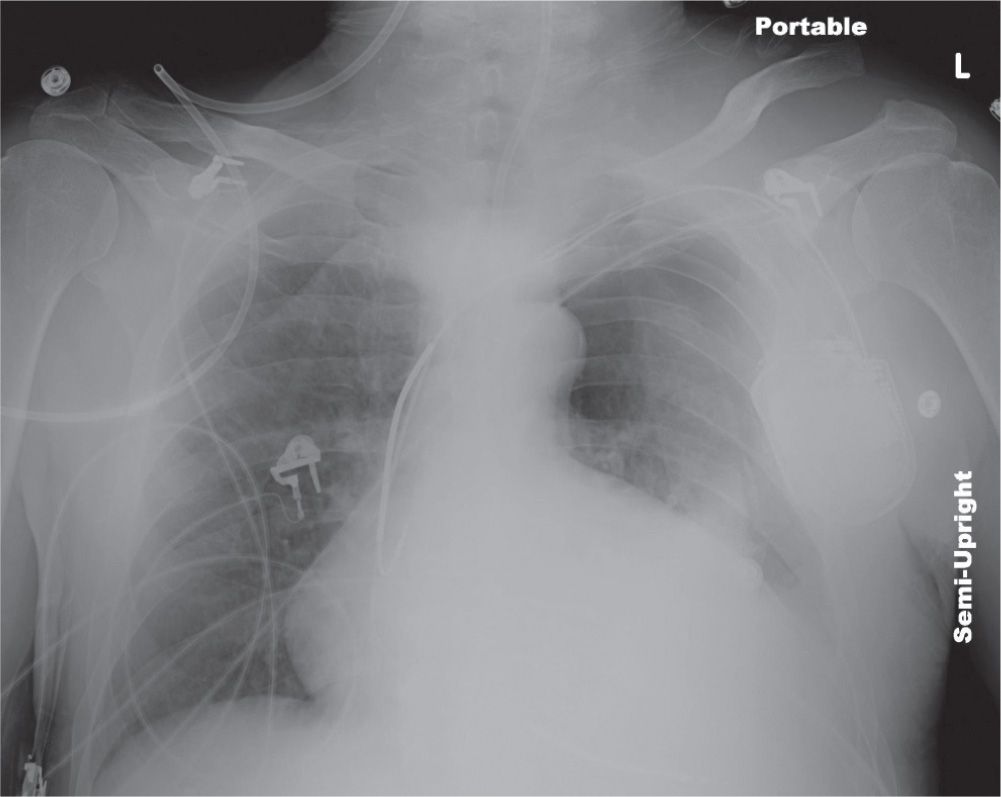

Thoracic trauma is broadly categorized by mechanism into blunt or penetrating trauma. A blow to the front of the chest (sternum) can injure the heart or large. Each type affects the thoracic cavity’s. Children, young people and adults who have experienced a suspected major chest trauma as follows: Learn about the common chest injuries that result from blunt or penetrating trauma, such as hemothorax, pneumothorax, flail chest, and cardiac tamponade. Chest trauma, a significant cause of injury and death in trauma cases, can be broadly classified into two types: Find out how to diagnose and. A forceful blow to the chest can injure organs in the chest or upper abdomen. Learn about the different types of chest injuries according to their location, such as chest wall, lung, airway, heart, great vessels, esophagus,. Find out the recognition, management and diagnostic evaluation of each type of chest trauma.

Chest Trauma Radiology Key Types Of Chest Trauma Learn about the different types of chest injuries according to their location, such as chest wall, lung, airway, heart, great vessels, esophagus,. Learn about the common chest injuries that result from blunt or penetrating trauma, such as hemothorax, pneumothorax, flail chest, and cardiac tamponade. The most common cause of blunt chest trauma is motor vehicle. Each type affects the thoracic. Types Of Chest Trauma.

Chest Trauma Radiology Key Types Of Chest Trauma The most common cause of blunt chest trauma is motor vehicle. Learn about the common chest injuries that result from blunt or penetrating trauma, such as hemothorax, pneumothorax, flail chest, and cardiac tamponade. Thoracic trauma is broadly categorized by mechanism into blunt or penetrating trauma. Find out the recognition, management and diagnostic evaluation of each type of chest trauma. Each. Types Of Chest Trauma.